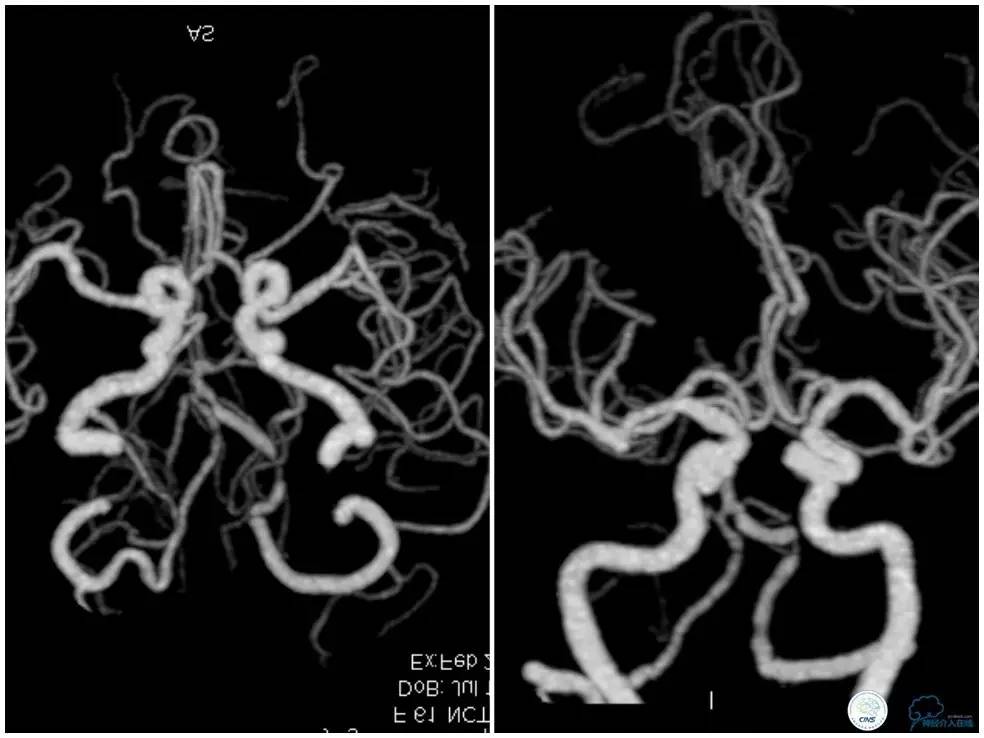

CTA(图3):双椎动脉、基底动脉、左侧大脑后动脉多发局部狭窄,以左椎动脉V4段为著。

图3